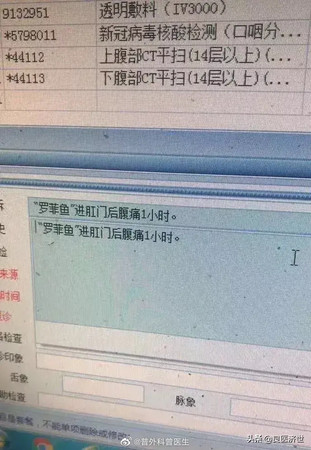

綜合中媒《封面新聞》報導,這名廣東病患因為肚子劇烈疼痛到醫院求診,他自述「不小心坐到魚上了」, 本來想要自己拿出來卻發現怎麼努力都沒辦法,魚依然卡在他的身體裡。先別說他怎麼會一絲不掛坐在魚上,醫護人員為了他的面子也沒有拆穿他。

醫院給他做了X光掃描,一照之下發現這條吳郭魚非常大,本來想要用內視鏡夾出,卻發現魚頭最寬的地方竟有3公分,魚鰭的刺還弄傷腸壁,醫生研判無法直接取出,只好開腹拿出。